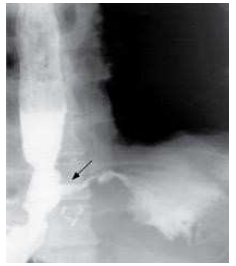

Perfuração esofágica

Figura 6: Perfuração esofágica com extravasamento de contraste

Perfuração Extravasamento de contraste Contraste hidrossolúvel

Condição Achados Conduta